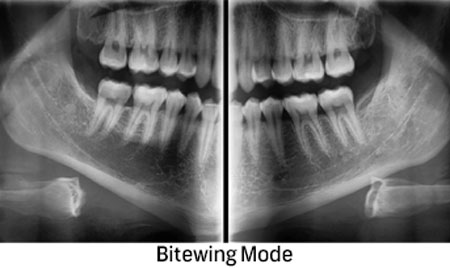

Преку нашите истражувачки активности, нашиот тим е запознаен со најновите научни наоди и може да ги исполни највисоките технолошки и професионални очекувања. За прегледи и проценки, имаме широк спектар на опции. Користиме различни методи за сликање, како што се проекциона радиографија, томографија и компјутерска томографија.

Kористиме најнова технологија за да овозможиме прецизен третман за нашите пациенти преку методи на снимање.